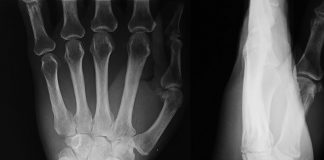

Ulnar Styloid Kırığı Akıl Kartı

Ulnar Styloid Kırığı izole olabilir veya radius distal uç kırığı gibi diğer yaralanmalara eşlik edebilir. Her tür kırıkta olduğu gibi ulnar stiloid kırığının ana...

Radial Styloid Kırığı Akıl Kartı

Elin radial kenarına uygulanan direk travmalar sonucunda radial styloid kısımda transver veya oblik şeklinde oluşan eklem içi kırık tipidir. AP grafide Radius styloidinin altında...

Rolando Kırığı Akıl Kartı

Rolando kırığı, başparmak metakarp kaidesinin eklem içi çok parçalı kırığıdır; “T” veya “Y” şeklinde olan tipleri ile karşımıza çıkar. Ayrılmamış kırıklarda alçı tespit için...

Bennett Kırığı Akıl Kartı

Bennett kırığı olarak bilinen patoloji aslında başparmak kaidesinin kırıklı-subluksasyonunu tanımlar. Redükte edilebilirse başparmağı içine alan kısa kol alçısı ile tespit edilebilir. Tespiti sağlanamayan kırıklarda...

Barton Kırığı

Radius alt uçunun intra-artiküler kırığı ile beraber dislokasyonudur. 1838’de Amerikalı cerrah ve ortopedist John Rhea Barton tarafından tanımlananmıştır. Çoğu vakada cerrahi redüksiyon gerektiği için...

Smith Kırığı

İlk olarak İrlanlandalı doktor olan Robert William Smith tarafından 1847 yılında tanımlanmıştır. Smith kırığı, distal radiusun volar (avuç içi) yöne açılanan kırığıdır. Muayenede el...

Colles Kırığı

Distal radius kırıkları genellikle el açık vaziyette yere düşme sonucu radius dorsale açılanması ile oluşur. Metafiz bölümünde oluşan basit tarzdaki kırıklardan, eklem içine ulaşan...